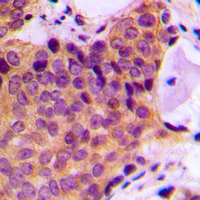

Immunohistochemical analysis of JNK1/2/3 (Phospho-T183) staining in human breast cancer formalin fixed paraffin embedded tissue section. The section was pre-treated using heat mediated antigen retrieval with sodium citrate buffer (pH 6.0). The section was then incubated with the antibody at room temperature and detected using an HRP conjugated compact polymer system. DAB was used as the chromogen. The section was then counterstained with haematoxylin and mounted with DPX. -